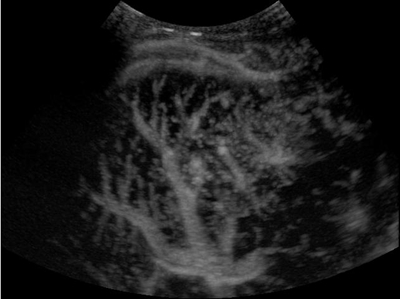

Mejora del microflujo

Vea mejor la perfusion de los vasos peque?os y mejore su comprensi├│n de la vascularidad de la patolog├Ła mediante el uso de varios marcos para generar im├Īgenes acumuladas.